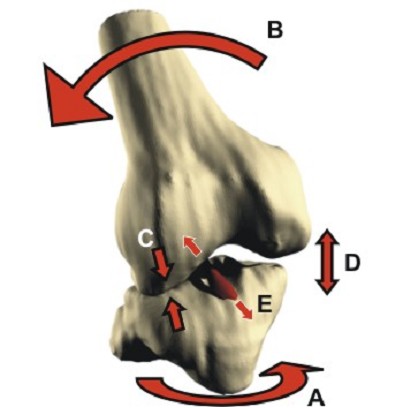

This term can be used to describe a high energy injury to the meniscus, usually in young patients. During the act of ligament rupture there is very rapid dissipation of energy with instantaneous displacement of the femur on the tibia "snap":-

This can cause severe damage to the meniscii either wrenching them from their attachment ("peripheral detachment") or by splitting off a large "bucket handle" segment. This is different to the common degenerative tear where a meniscus has gradually become weaker and weaker to finally fail following a trivial injury ("the straw that broke the Camel's back").